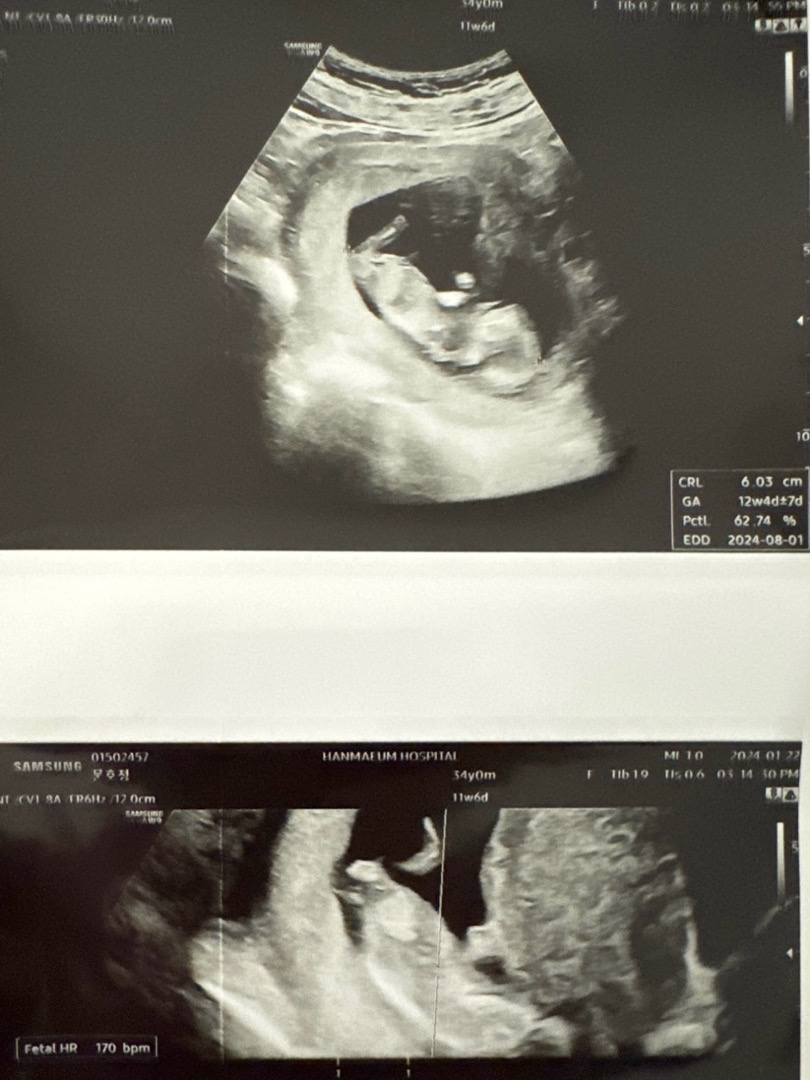

12주차 각도법으로 보이나용...?( Ĭ ^ Ĭ )

이걸로 각도법 볼수있는분 계실까요...?? 너무너무 궁그매용 ㅜ 알려주세욤 ᐕ

딸같기도해요 ㅋㅋㅋ…장꾸맘카페 가입해보세요!